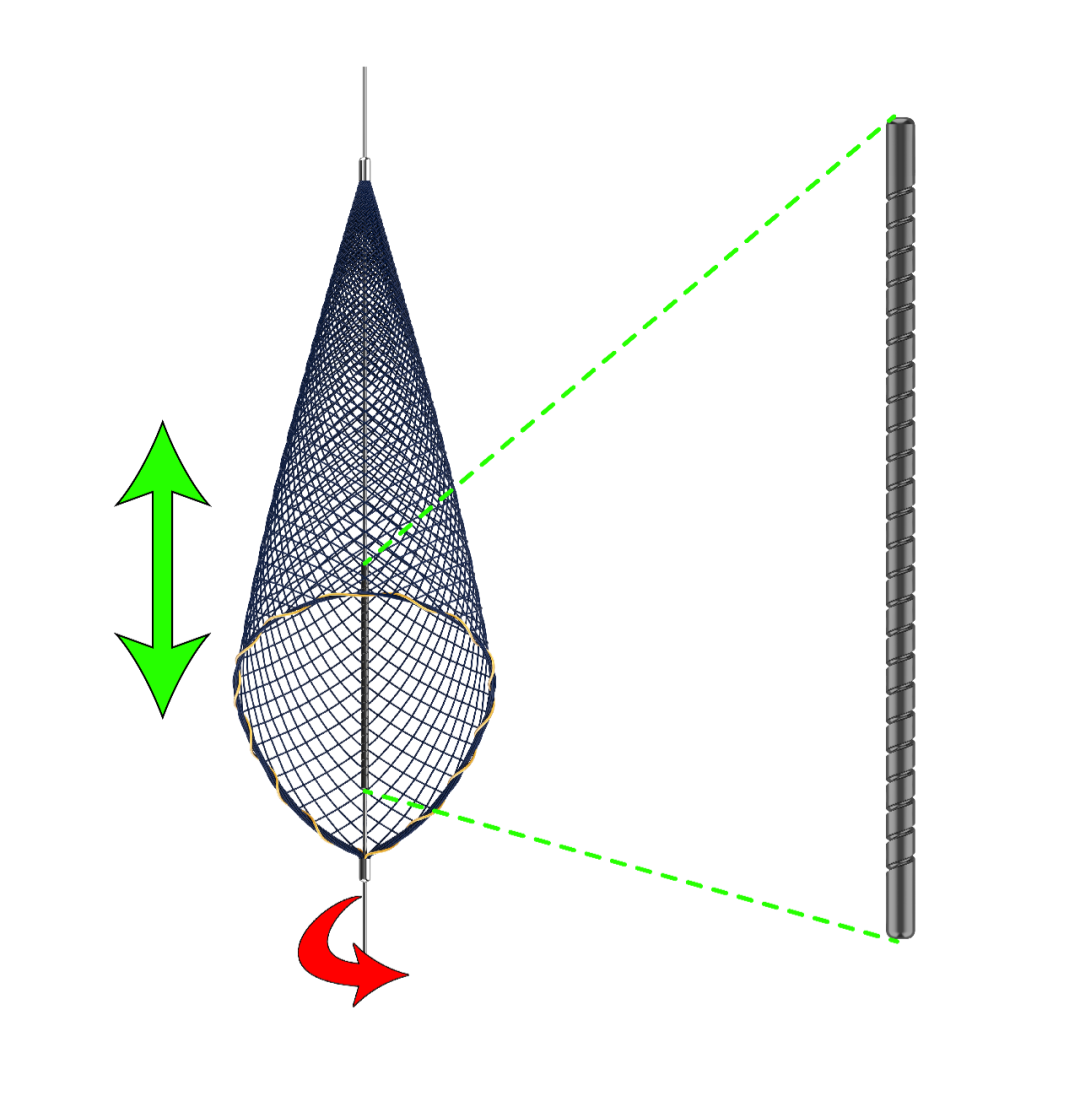

独立导丝允许导丝可以做一定幅度的旋转或轴向运动。避免已释放的滤网发生位移,损伤血管内壁引发血管痉挛。固定套管经过激光螺旋切割处理,提高了柔软度,更有利于通过迂曲血管,释放伞时也更加贴壁。

输送鞘管采用分段的硬度设计,远端更软,同时具有出色的抗弯折能力。回收鞘管拥有更大的内腔直径,全段PTFE涂层,摩擦阻力只有同类产品的50%。一体化的输送鞘管和回收鞘管,可与0.014″ 导丝兼容,实现术中快速交换。